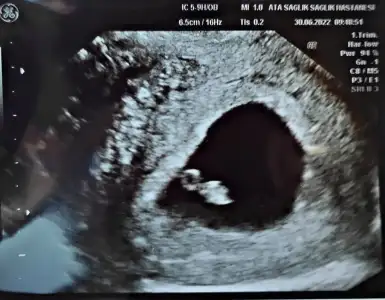

Peki sence bu ney 8 haftalık karından

Hissime göre söylüyorum kız mı buPeki sence bu ney 8 haftalık karından